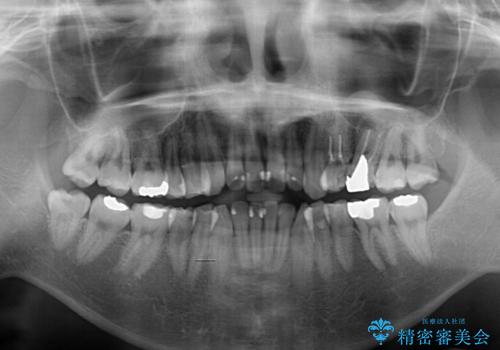

- ボロボロのむし歯とデコボコの歯列を気にして来院された患者様です。

ボロボロとなっていた歯は抜歯が必要な状態でしたが、舌側転位している歯を移動させることで抜歯スペースを埋めることができるため、矯正治療により歯列を整えることとしました。

舌側転位の改善にインビザラインを用いるのはやや難易度が高くなりますが、前歯部のデコボコは軽度であったため、インビザラインによる矯正治療を行うこととしました。

矯正治療後には抜歯が必要な歯に隣接してむし歯となっていた歯をオールセラミッククラウンにて補綴治療を行うこととしました。